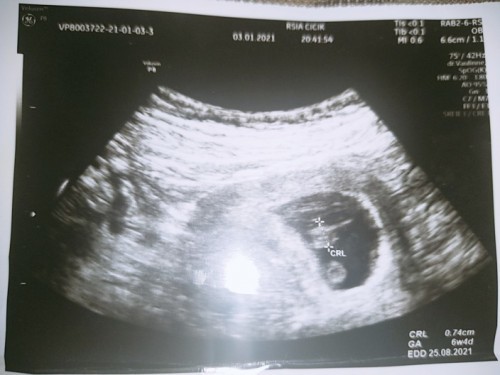

Kenapa USG sama perkiran bidan berbeda, kalo USG 10 Wek kalo bidan 15 Wek, kenapa bisa seperti itu

haidnya teratur gak bu? kalau ga teratur hitungan usia kehamilannya jg jd ga akurat